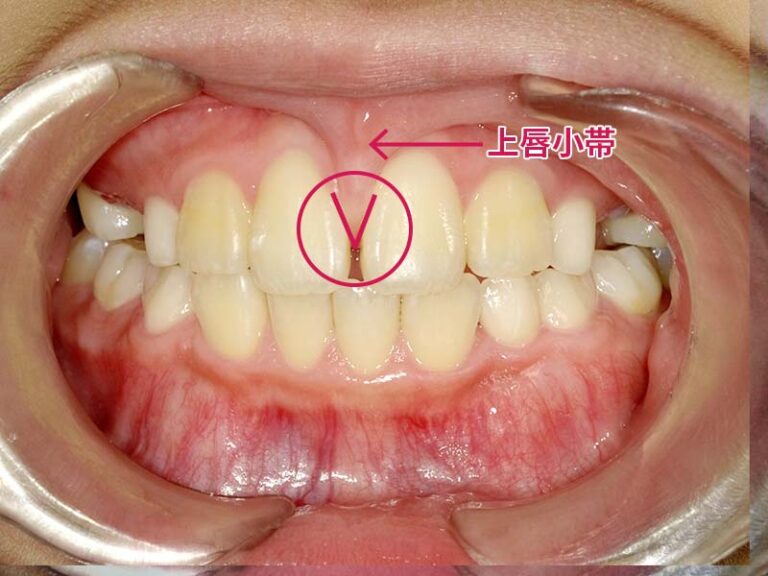

上唇小帯の位置異常

上唇小帯とは、上唇と歯茎をつなぐヒダのことを指し、上の前歯の真ん中に隙間があることを「正中離開」と言います。生後すぐは非常に発達しており、成長とともに徐々に小さくなりますが、ときどき、この小帯が小さくならないことがあり、上の前歯がすきっ歯になるケースがみられます。

上唇小帯による正中離開がみられる場合でも、成長とともに上唇小帯の位置が変化することで、自然に隙間が閉じていくケースもあります。しかし、自然治癒が難しい場合には、上唇小帯を少し切除し、矯正装置を付けて隙間を閉じる治療を行うこともあります。

上唇小帯の症状の写真